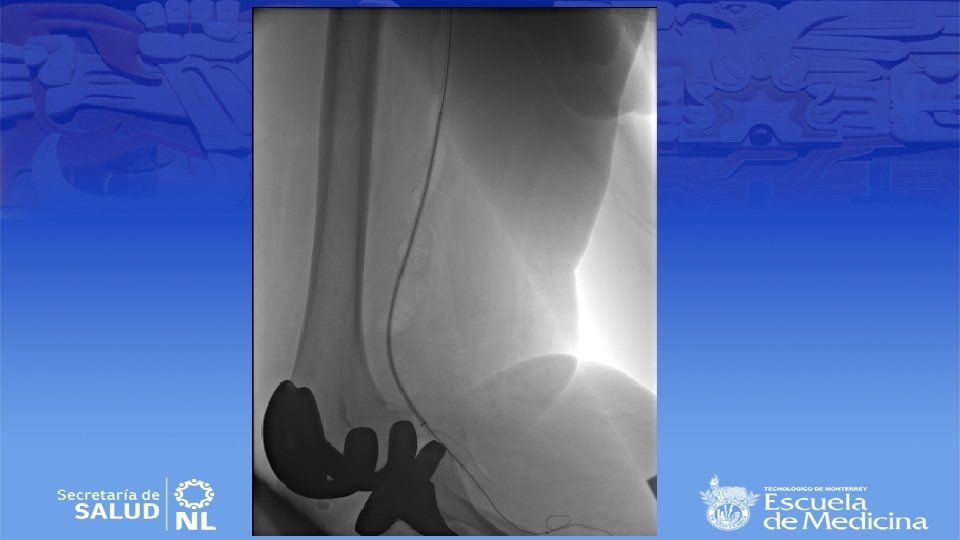

Diagnostico • Ultrasonido Doppler, Angiotac, angioresonancia • Arteriografía es mas apropiada para sintomatología aguda

Indicaciones quirúrgicas • Sintomáticas (60 – 74% presentan síntomas) – Isquemia aguda de extremidad, independientemente del tamaño. • Asintomáticas – Aneurismas mayores a 2 cm de diámetro • Relativas • Aneurismas menores de 2 cm asintomaticos con trombosis asociada • Se prefiere cirugía convencional a cirugía endovascular

Cirugía endovascular • Para pacientes con alto riesgo quirúrgico • Deben de tener al menos 2 cm de arteria proximal y distal sin patología para anclar la endoprótesis • Se repite la angiografía durante el procedimiento para selección de la endoprótesis correcta • Debe de ser 10 a 15% mas grande que el diámetro del vaso